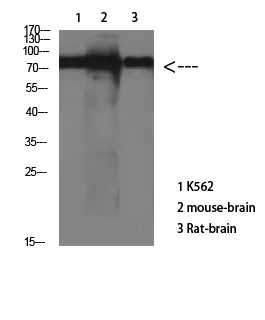

ERK1/2(1H4)Mouse Monoclonal Antibody

Cat: AMM10602

Size1:50μl Price1:$128

Size2:100μl Price2:$230

Size3:500μl Price3:$980

Size2:100μl Price2:$230

Size3:500μl Price3:$980